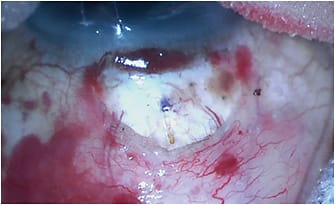

Ab-externo delivery can be performed through either a closed conjunctiva (transconjunctival) or an open conjunctiva via a peritomy. In the ab-externo transconjunctival approach, the 27-gauge needle tip of the Xen 45 injector is used to pierce through the conjunctiva 7-10 mm posterior to the limbus and advance through the subconjunctival space. Then, it pierces through the sclera 2 mm to 2.5 mm posterior to the limbus at a shallow 15° angle to enter the anterior chamber just anterior to the trabecular meshwork and then deploy the Xen. The Xen can then be adjusted through the conjunctiva with toothless conjunctival forceps if necessary. This technique benefits from a corneal traction suture or other means to dramatically infraduct the eye, which appears to be a noninferior technique to traditional ab-interno approaches, while lowering the needling rate.10

Ab-externo Xen through an open conjunctiva is the final approach. In a way, one could argue that this approach violates the “minimally invasive” concept of the Xen. However, its advocates tout a much lower needling rate than with the traditional ab-interno approach. The disadvantages of opening the conjunctiva, having to apply cautery, and then closing the conjunctiva are offset by an unobstructed view of the device entry into the sclera and the freedom to easily manipulate the Xen after implantation for optimal placement. Mechanically clearing out a space for aqueous to accumulate under Tenon’s capsule and preventing entanglement of the stent within Tenon’s capsule are major advantages to this approach.11